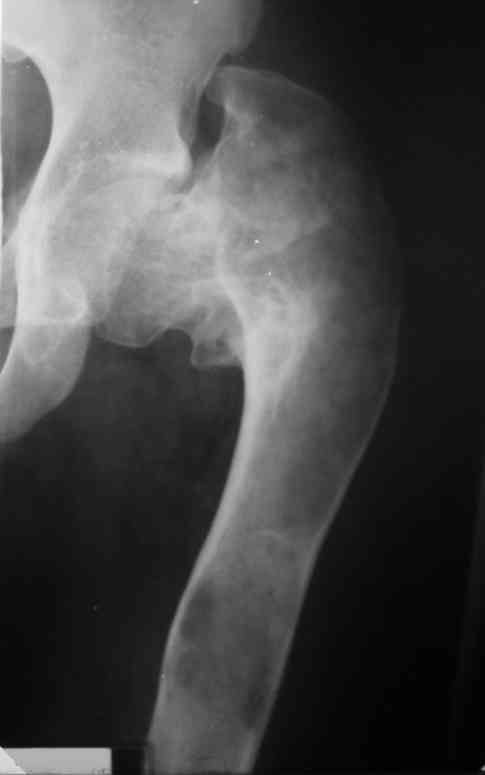

Re: Сросшийся патологический перелом шейки бедра - выбор тактики лечения

Около 16 лет наблюдаю пациента с ФИБРОЗНОЙ ДИСПЛАЗИЕЙ левой нижней конечности, полиосальная форма. Прилагаю рентгенснимки.